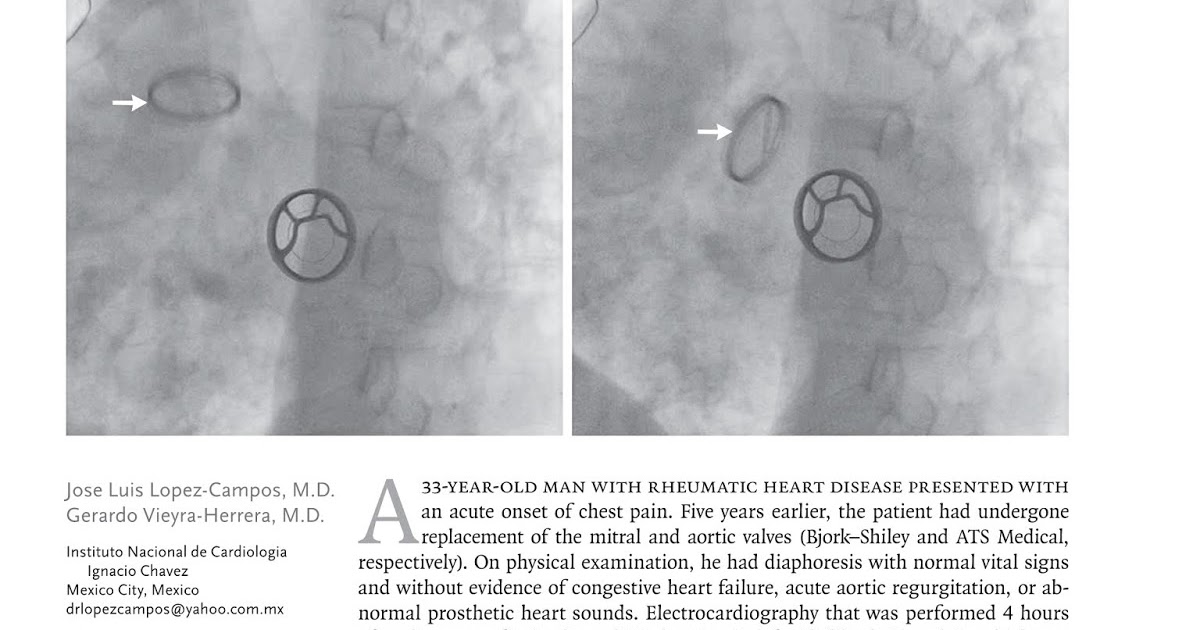

Acute dehiscence of a valve prosthesis 5 years after implantation Valve Dehiscence Definition each case with potential hemodynamic valve deterioration should be individually adjudicated to confirm presence, stage, and etiology. the index case had valve dehiscence with paravalvular. the dehiscence of prosthetic aortic valve is an uncommon complication,. the dehiscence of prosthetic aortic valve is an uncommon complication, occurring in 0.1% to 1.3% of patients. Valve Dehiscence Definition.